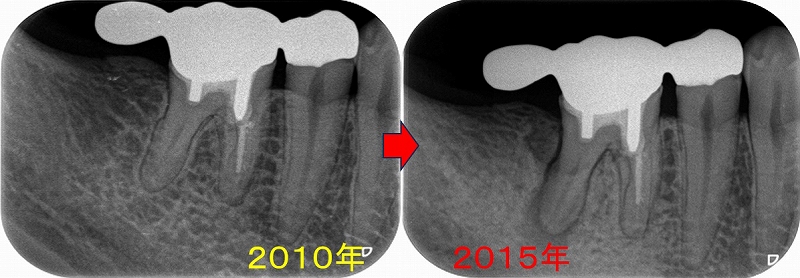

根尖孔外感染で外科的歯内療法が必要と思われた1ケース

患者さんは50代女性

レントゲン

2026 EEdental SMA (1).jpg

根尖病変が見られ、根尖には吸収とセメント質の添加のような所見があり、

長い間根尖病変があったように思えます。

このように根尖の形が変わっていると、根尖孔外感染を疑うことをします。

本来根尖病変は歯の中の細菌感染で起こっていることが殆どですが、稀に歯の外にも細菌がコロニーを作り歯の外も外科的に掃除しないと治らないことがあります。

ただ、個人的にはそのような所見があってもまずは根管治療からスタートすることが殆どで

根管治療で治らない場合に外科処置に踏み切ります。

この辺りは歯内療法専門医でもマチマチで、外科介入で早期に決着を付ける先生もいます。

このぐらいの長さのメタルコアに関しては、難なく外せるのでコア除去のリスクは高くはありません。

長目に時間をもらい2本を1回法で治療

2026 EEdental SMA (2).jpg

根尖は吸収があり根尖が大きく開いていたのでMTAセメントを使用

ここから仮歯で経過観察

術後1年

2026 EEdental SMA (3).jpg

レントゲンでは骨は出来てきてくれています。

この状態であれば外科的歯内療法せずにもう少し待ってみましょうと提案

術後2年

2026 EEdental SMA (4).jpg

腫れなどもなく、骨も出来てきているので仮歯から本歯に入れ替えることに

術後

2026 EEdental SMA (5).jpg

ここまで骨が出来ればもう大丈夫でしょう!

根尖の形は病変のなかった右側に比べると左右差はありますが、

2026 EEdental SMA (6).jpg

問題はありません。